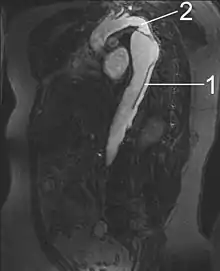

أشعة الرنين المغناطيسي (MRI)

تعد أشعة الرنين المغناطيسي (التصوير بالرنين المغناطيسي) حاليًا هي أفضل اختبار للكشف عن تسلخ الأبهر وتقييم حالته، حيث تبلغ نسبتي خاصيتي الحساسية والنوعية لهذا الاختبار %98. يقدم التصوير بالرنين المغناطيسي صورة تركيبية ثلاثية الأبعاد للشريان الأبهر، مما يسمح للطبيب أن يحدد موقع الجزء المتمزق من البطانة الداخلية للشريان، ومدى إصابة الأوعية الدموية الفرعية، ويحدد ما إذا كانت هناك أية أجزاء ثانوية أخرى تعرضت للتمزق. تعد هذه الأشعة من الاختبارات غير الجراحية، ولا تتطلب استخدام مواد تباين معالجة باليود، إضافة إلى قدرتها على تحديد درجة قصور الأبهري بدقة بالغة.

يتمثل العيب الوحيد لاستخدام أشعة الرنين المغناطيسي في الكشف عن تسلخ الأبهر في عدم توفرها بالقدر الكافي الذي يسمح لكافة الحالات المصابة بتسلخ الأبهر باستخدامها حيث أن جهاز أشعة الرنين المغناطيسي - في كثير من الأحيان - لا يوجد إلا في المستشفيات الكبرى، إضافةً إلى أن إجراء أشعة الرنين المغناطيسي يستغرق وقتًا طويلاً نسبيًا. ونظرًا للكثافة العالية للمجالات المغناطيسية المستخدمة في أثناء التصوير بأشعة الرنين المغناطيسي، فإن التصوير بالرنين المغناطيسي لا يصلح لمن لديهم أجهزة أو أجزاء معدنية مزروعة في أجسادهم نتيجة لإصابات أو إجراء جراحات أو ما شابه. علاوةً على ذلك، يعاني الكثيرون من الخوف من المناطق المغلقة في أثناء وضعهم في داخل أنبوب جهاز أشعة الرنين المغناطيسي.